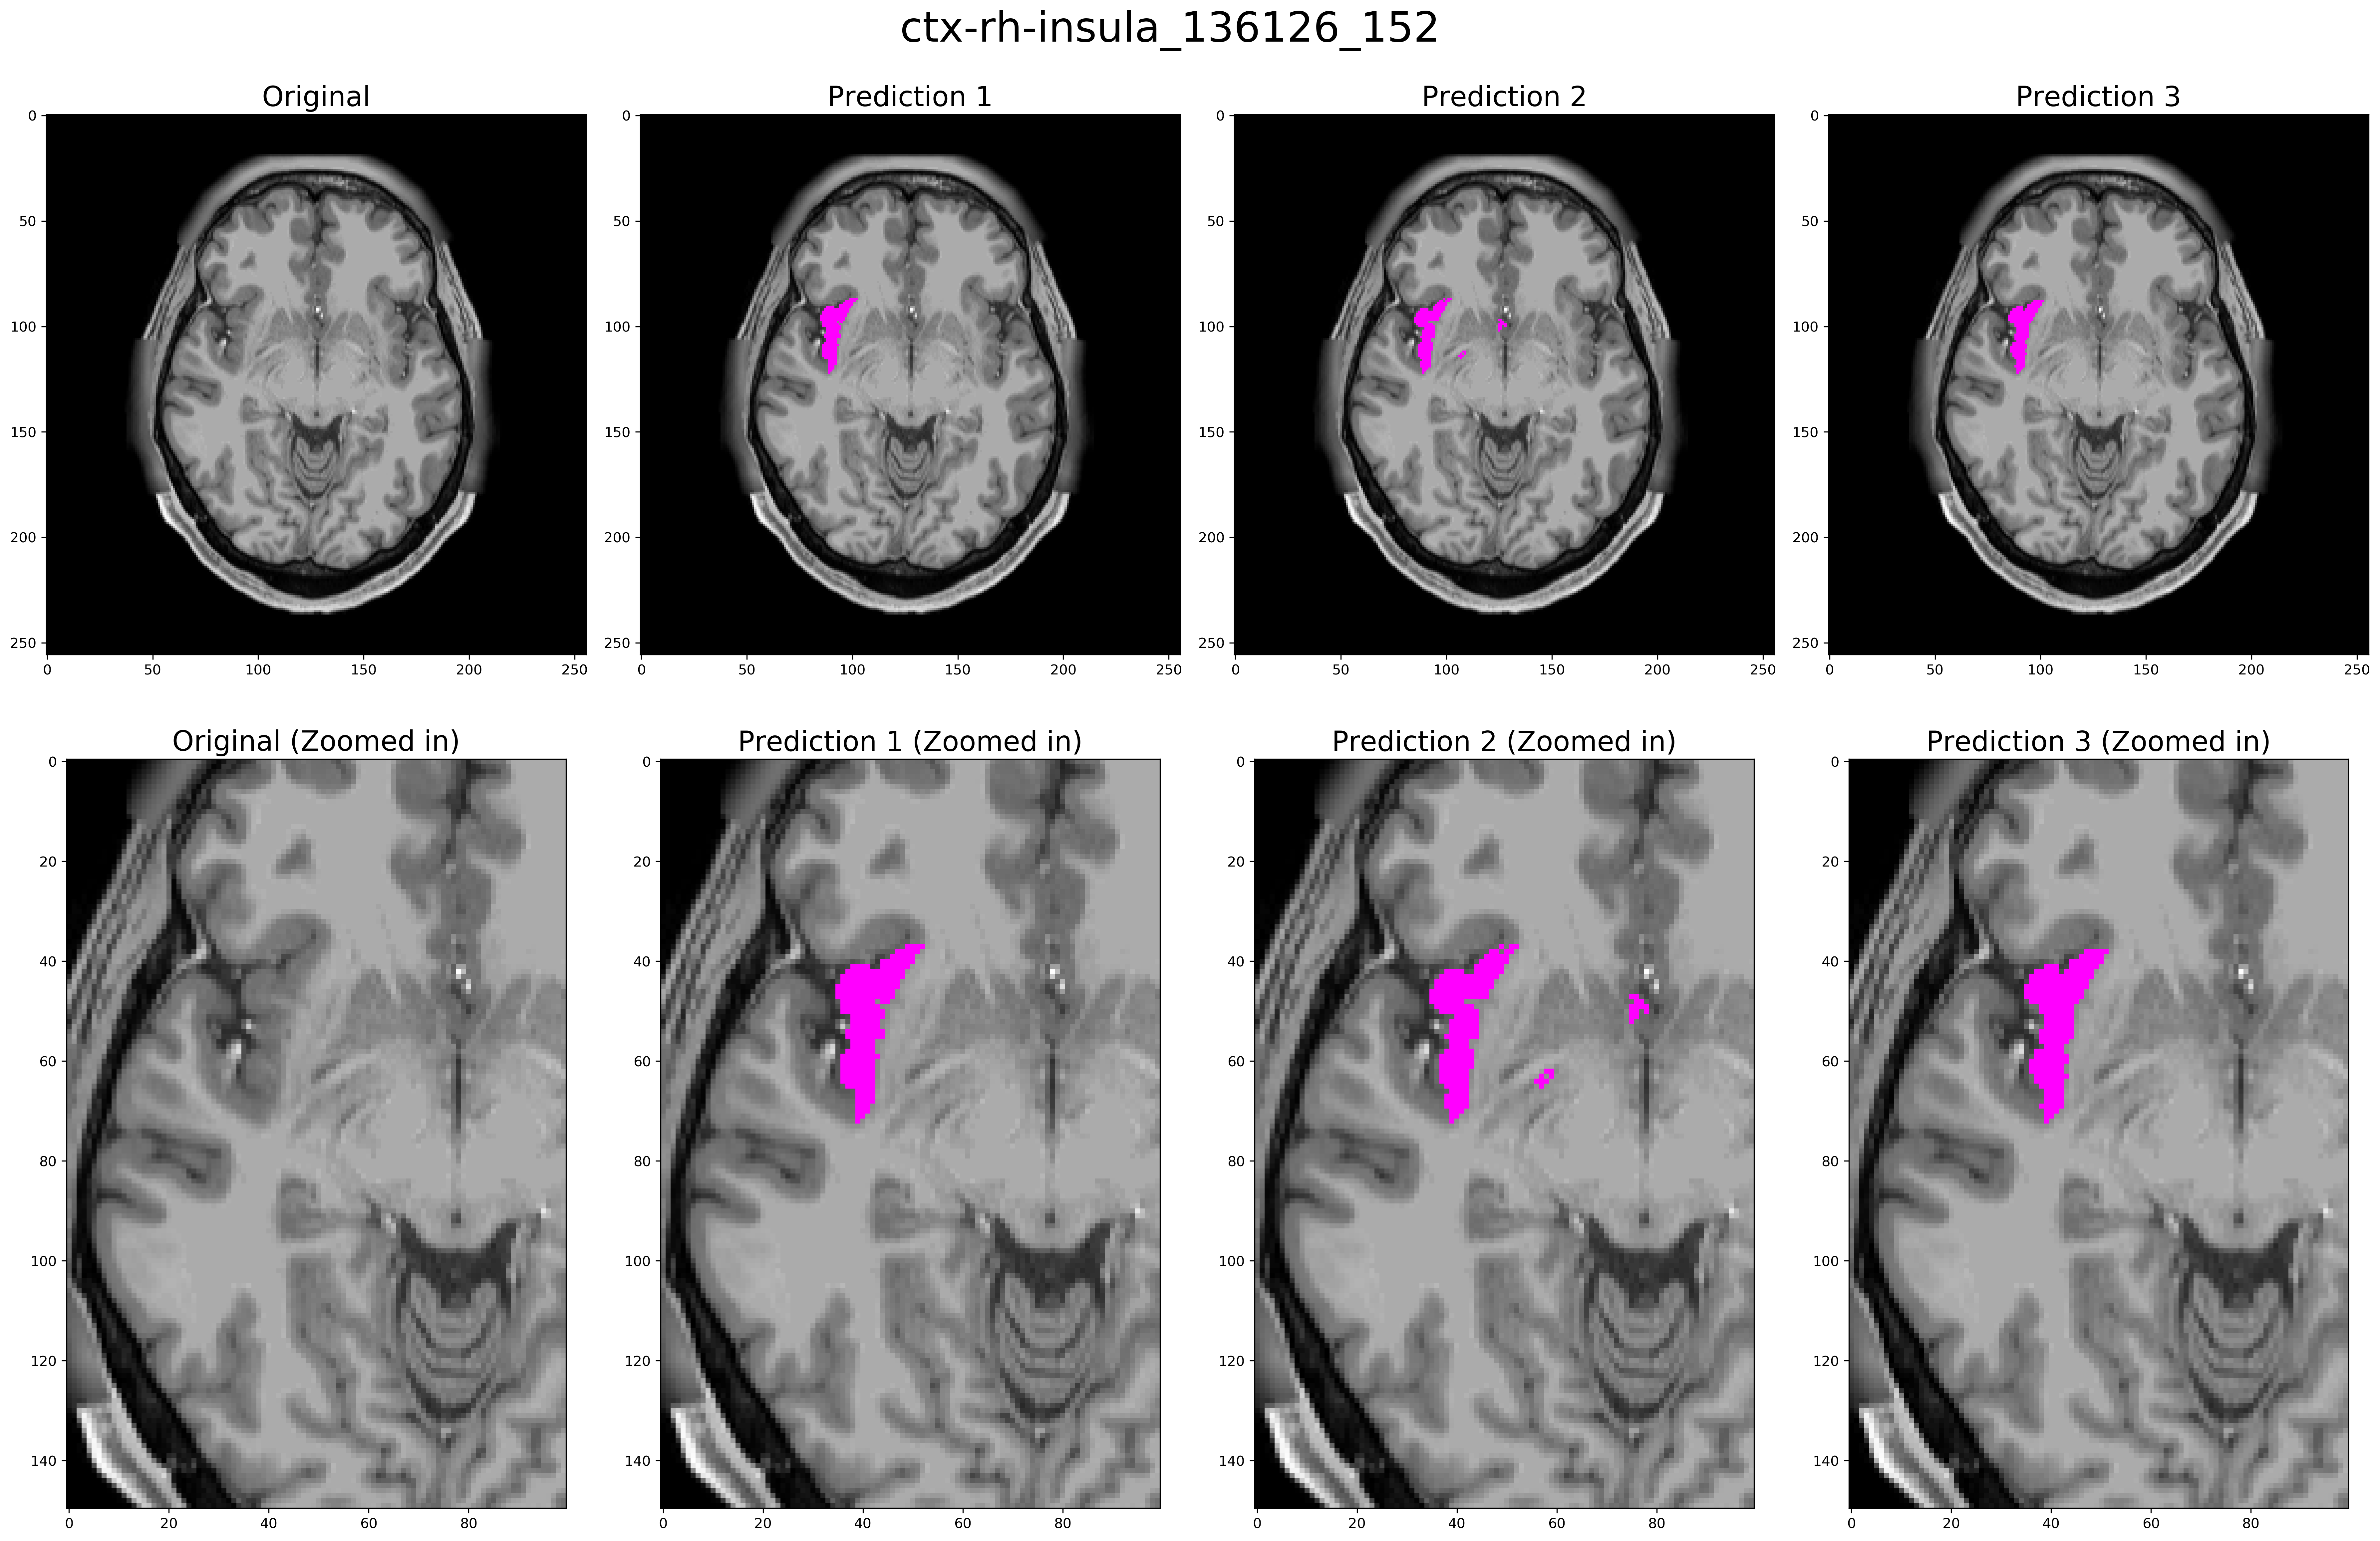

Three expert readers performed visual inspection and assessment of the segmentation results. There were two attending neuroradiologists with 3 and 5 years of experience and one second-year radiology resident. Each reader was asked to rate 40 different predictions for each ROI (20 in each brain hemisphere) such as shown in figure 2. Readers were blinded to the algorithm used to predict the segmentation and examples were presented in a randomized order. Each prediction presented consisted of a single slice containing a minimum of 40 pixels within the ROI, ensuring that enough of the structure being assessed was present on the given image. A sample slice rated by the readers is shown in figure 2.

Refer to caption

Figure 2: A sample segmentation of Right Insula used in the expert reader evaluation. Here, predictions 1, 2 and 3 are from the Finetuned model, Freesurfer, and non-Finetuned model respectively; though in the reader study, numbering and order of presentation of the predictions are randomized and a total of 280 of examples are presented. Each reader is asked to rate each example for the quality of segmentation on a 5-point Likert-type scale.